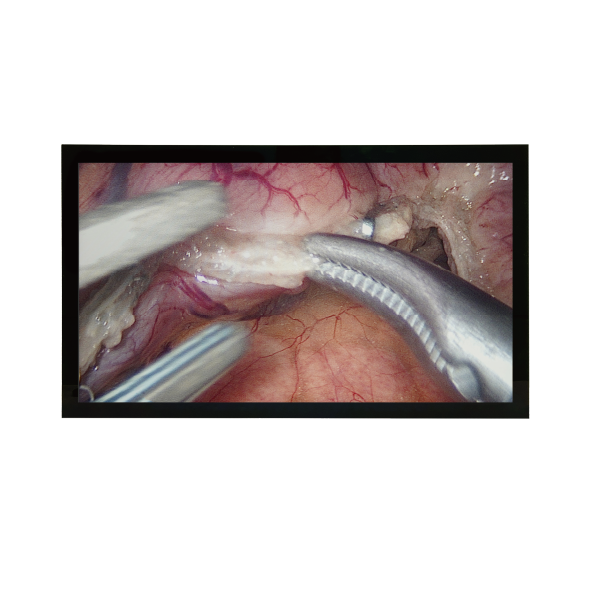

The BDS Medical Monitor Series (available in 21.5", 23.8", and 27") includes both touch and non-touch models. These monitors offer a variety of digital image I/O interfaces, including DisplayPort, HDMI, and DVI, allowing for the flexible integration of various medical imaging and clinical systems. The products comply with DICOM Part 14 and Gamma 2.2 display standards, ensuring stable, consistent accuracy and reliable image quality. Their high-contrast design clearly distinguishes between light and dark levels. Furthermore, they have passed multiple medical regulatory certifications, meeting safety standards for medical equipment in clinical environments.